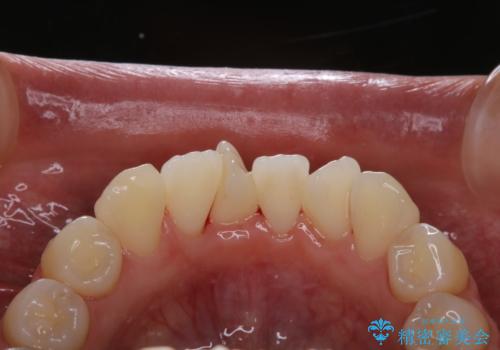

矯正治療開始前のPMTC

- 矯正カウンセリング、矯正検査後にクリーニング希望で来院されました。しばらく歯科医院にて、クリーニングを行ってなく、歯石やステインが気になるとのことでした。PMTC(自費クリーニング)30分コースを行いました。

矯正治療は、歯を動かすため歯ぐきにもかなりの負担がかかります。そのため歯列矯正の前にはしっかりとしたクリーニングを行い、歯ぐきのコンディションも整えることが大切です。また、歯石やステイン(着色)が歯についたままだと、矯正の装置が、適切に設置できなかったり、装置が外れやすくなってしまったりとトラブルの原因になることがあります。矯正治療中に歯周病や虫歯にならないためにも、専門的なクリーニングを行うことが大切です。